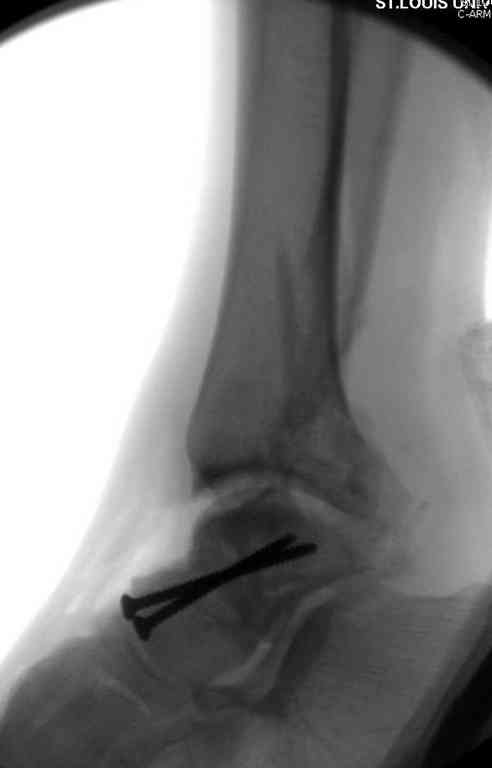

Вчера провели фиксацию.

Из-за многооскольчатости дистальной части малоберцовой, где невозможно было провести фиксацию шурупами, перелом зафиксирован подпирающей пластиной, которая должна служить дополнением отсутствующей дистальной части малоберцовой (lateral cortex substitute).

Для стабильности два шурупа на синдесмоз.

Медиальную рану с приближенными краями продолжаем вакуумировать (KCI). Наружный фиксатор оставлен на пару недель, надеюсь, небольшая рана будет гранулировать и закроется без кожной пластики. Фиксация медиальной ложыжки не планируется.